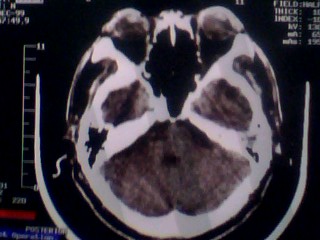

以下是引用随光逐影在2010-1-7 14:49:00的发言:[br]1)结合病史,考虑多发性脑转移瘤可能性大;建议行ct增强扫描检查。2)大脑镰下疝。3)脑积水。